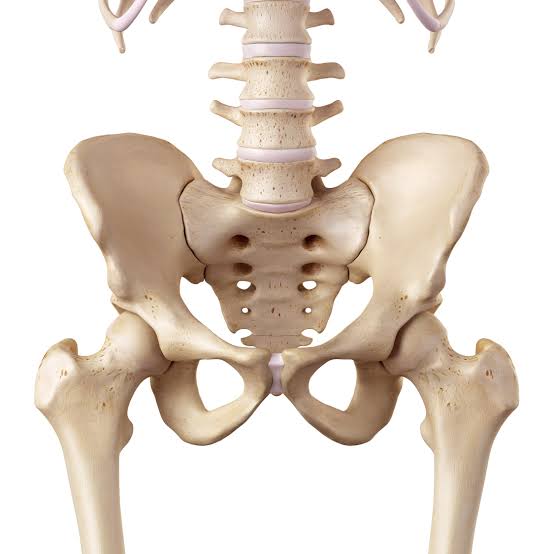

पेल्व्हीॲसीटॅबुलर ट्रॉमा

कटी किंवा ॲसीटॅबुलम (जिथे हिप सांधा असतो) यातील हाडांचे तुटणे हा ऑर्थोपेडिक सर्जनांद्वारे उपचार केला जाणारा एक गंभीर प्रकार आहे. हे प्रामुख्याने रोडवर होनारे अपघात, उंचावरून पडणे यासारख्या मोठ्या आघातामुळे होते. अशा फ्रॅक्चरवर त्वरित आणि अचूक उपचार आवश्यक असतात, आणि काही वेळा एक किंवा अधिक शस्त्रक्रिया करावी लागते. सर्व वयोगटांतील लोकांना हे दुखापत होण्याचा धोका असतो. तसेच, वृद्ध व्यक्तींमध्ये हाडांची ठिसूळता (ऑस्टिओपोरोसिस) असल्यास कमी प्रभावी आघातानेही पेल्व्हिक किंवा ॲसीटॅबुलम फ्रॅक्चर होऊ शकते.

फ्रॅक्चर झालेल्या कटी (पेल्व्हिस) चे स्वरूप:

कटी म्हणजे शरीराला आधार देणारी आणि अंतर्गत अवयवांचे संरक्षण करणारी हाडांची रिंग आहे. ती मोठ्या आघातामुळे कोणत्याही ठिकाणी फ्रॅक्चर होऊ शकते.